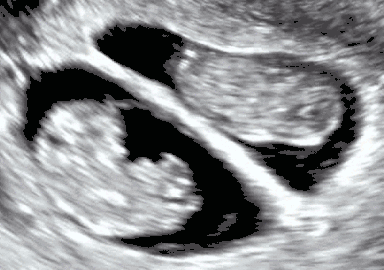

Obstetric ultrasonography of twins at a gestational age of almost 9 weeks. The mother’s and the twins’ bodies have a higher echogenicity than the amniotic fluid around them. The standard representation is brighter color for higher echogenicity, giving the almost anechoic fluid an almost black appearance.

Echogenicity (sometimes as echogenecity) or echogeneity is the ability to bounce an echo, e.g. return the signal in medical ultrasound examinations. In other words, echogenicity is higher when the surface bouncing the sound echo reflects increased sound waves. Tissues that have higher echogenicity are called "hyperechoic" and are usually represented with lighter colors on images in medical ultrasonography. In contrast, tissues with lower echogenicity are called "hypoechoic" and are usually represented with darker colors. Areas that lack echogenicity are called "anechoic" and are usually displayed as completely dark.[1]